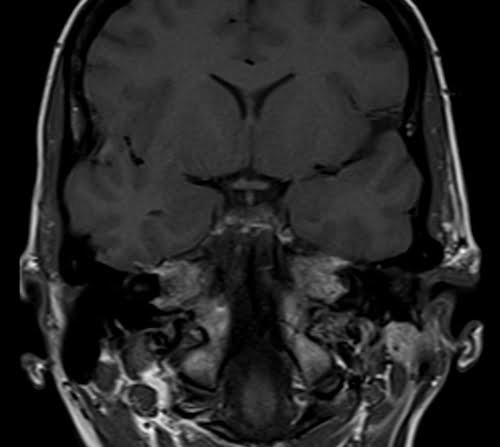

Brain epilipsy protocol mri coronal T1 images